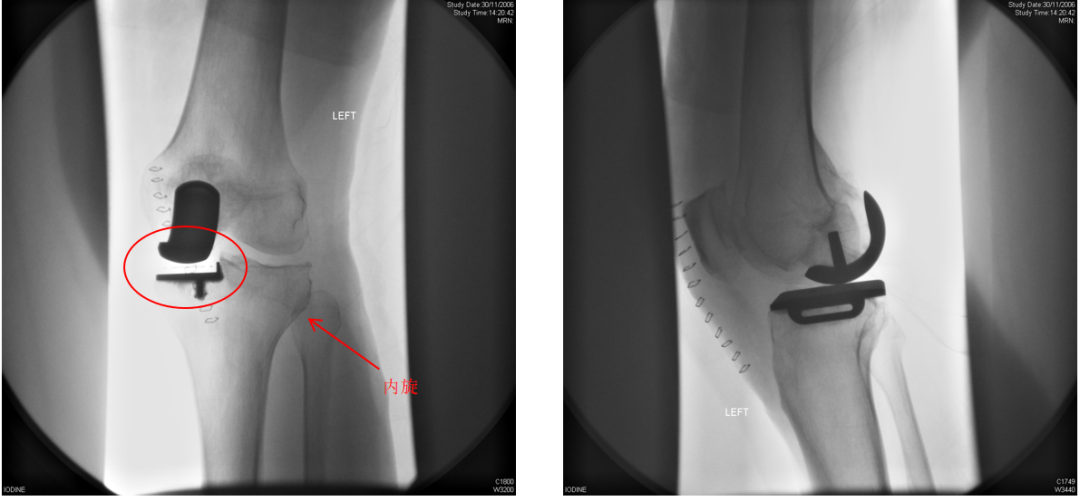

病例1

术后X-ray:正位片内旋,显示胫骨假体大小及位置佳(垂直截骨在棘突顶点、与内侧缘齐平、无内外翻)。

病例2

术后X-ray:标准正位片,显示胫骨假体大小及位置佳(垂直截骨在棘突顶点、与内侧缘齐平、无内外翻)。